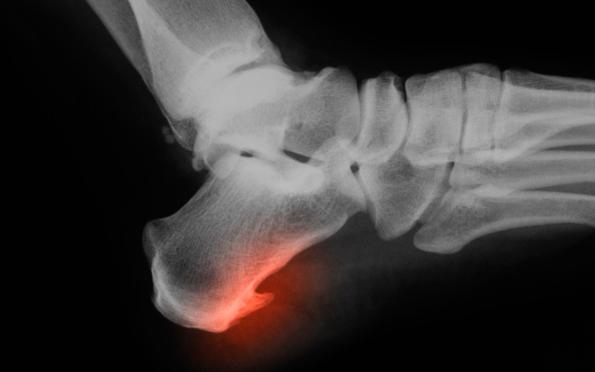

常见的有踝关节(脚部跟骨)附近的骨刺、膝关节半月板附近的骨刺、脊柱骨刺等等。

比如最常见的脚部足跟骨刺,可能会引起脚跟痛。